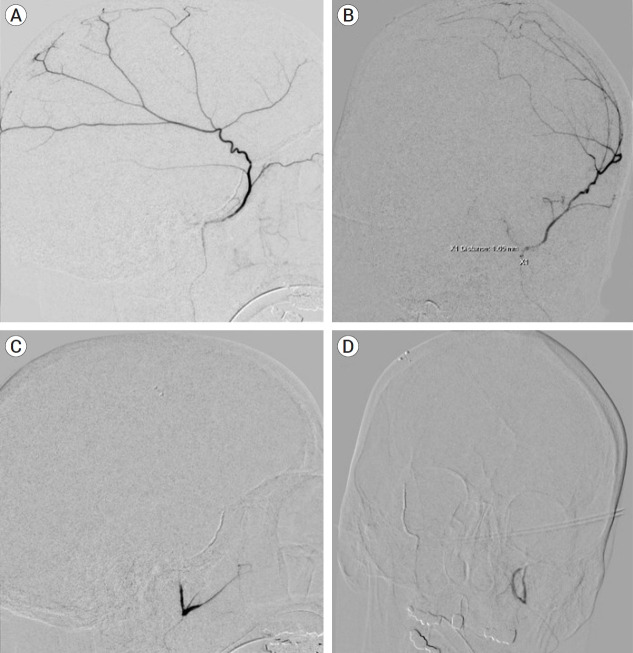

Methods: Four patients (3 females, 1 male, median age 77.5) with bilateral subdural hematomas were treated with bilateral MMA embolization. One hematoma of each patient was treated with coils and PVA, and the other was treated exclusively with coils. New or resolved symptoms, radiographic imaging demonstrating hematoma change, and complications were recorded and compared between the two treatment modalities. Minimum follow-up time was three months.

Results: All patients demonstrated symptomatic and radiographic improvement at three month follow-up. None of the patients in this cohort received surgical evacuation of the hematoma prior to or after embolization. One patient had previously been treated for hydrocephalus with a VP shunt. There were no postoperative complications. In the hematomas treated with a combination of coils and particles, three showed complete resolution with one showing interval improvement on imaging. All hematomas treated with coils alone demonstrated complete resolution after three months. Conclusions: Middle meningeal artery embolization with coils alone has demonstrated noninferior results to embolization with a combination of particle embolisate and coils in this small cohort.